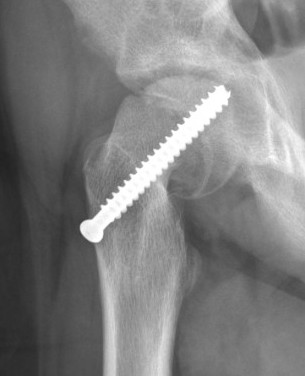

Fixation failure

Cam FAI

Mechanism

Epiphysis heals in a posterior and inferior position with moderate - severe slips

Abnormal contact of relatively anterior neck on the acetabulum